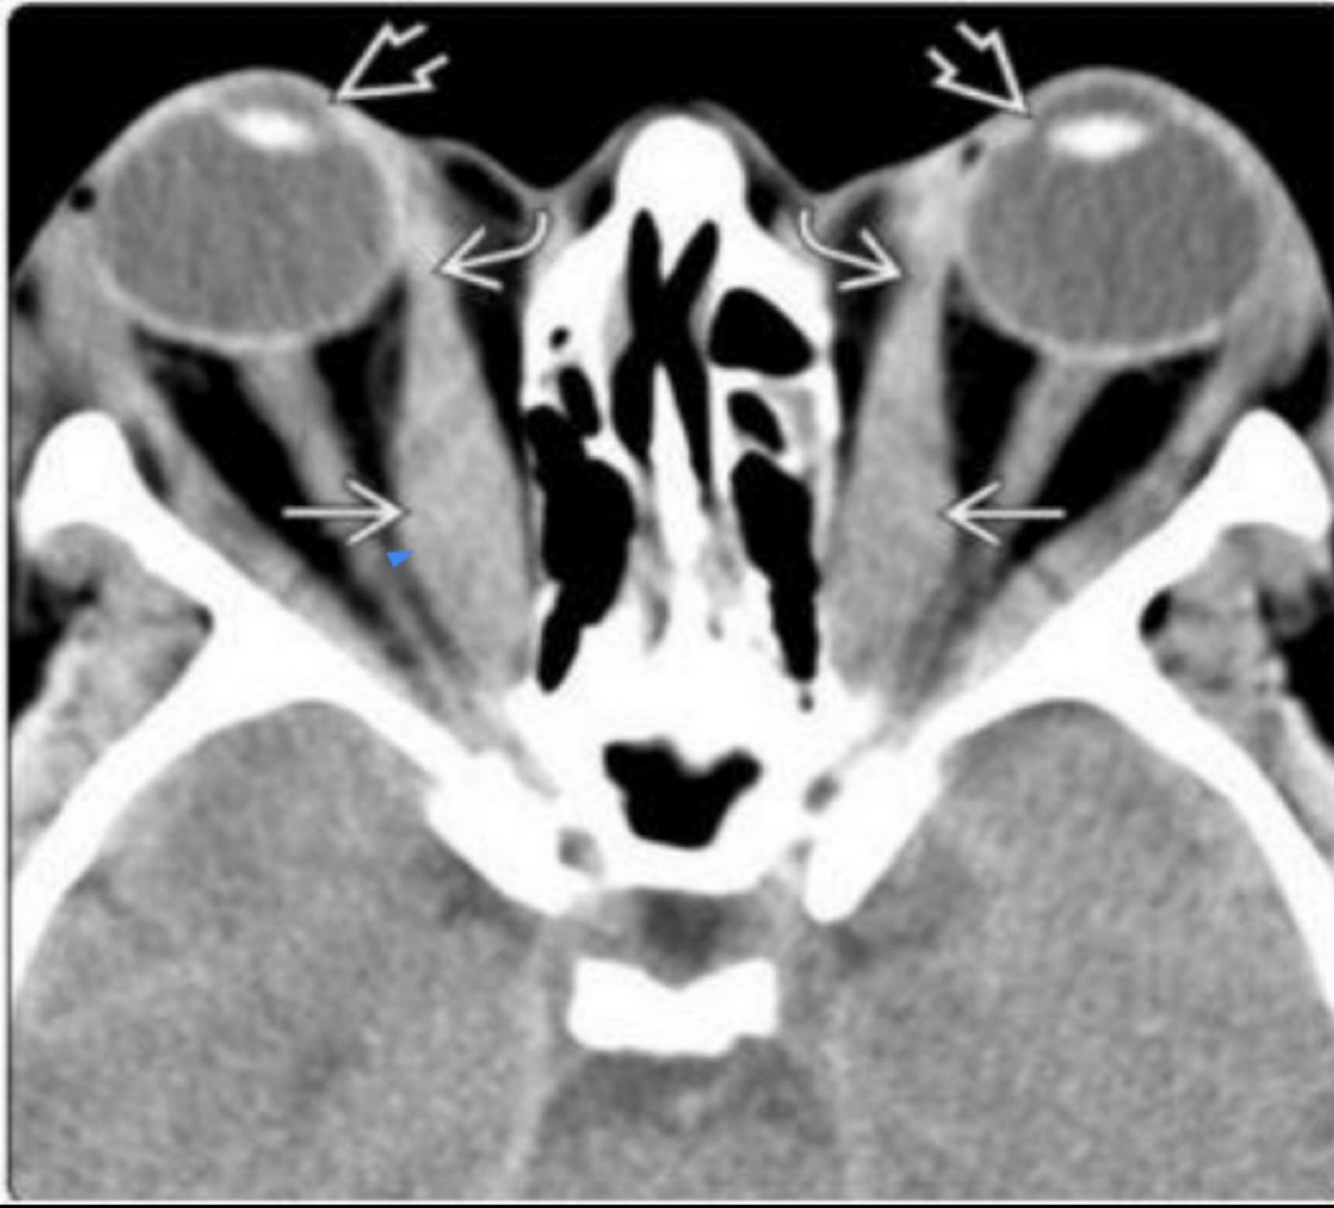

Q

Desprendimiento de retina

Hallazgos en TC/MRI

A

• Hiper densidad/intensidad

• Fluido subretiniano

• Neoplasias

• Retina triangular

Hallazgos de USG en deprendimiento de retina:

• Retina doblada y brillante

• Movimientos disminuyen con tiempo

• Forma triangular en humor vítreo (sangre)